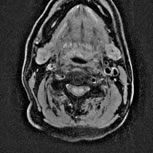

MRI検査とは?

MRI検査とは、強力な磁石と電磁波を使って、身体の任意断面画像を得る検査です。CT検査と異なり、放射線を使用しないため、人体への影響がなく全身の検査が可能です。特に脳、脊髄、血管、下腹部、四肢の検査が多く行なわれています。

MRスペクトロスコピー

MRスペクトロスコピーとは生体内に存在するプロトン原子の、共鳴周波数の差を利用することにより、生化学的な解析を行うものです。組織を取り出すことなく細胞の代謝(細胞の生命活動)の状態を測定したり、原子の数を測定したりします。

脳の場合では、脳腫瘍の悪性度の評価などに応用しています。